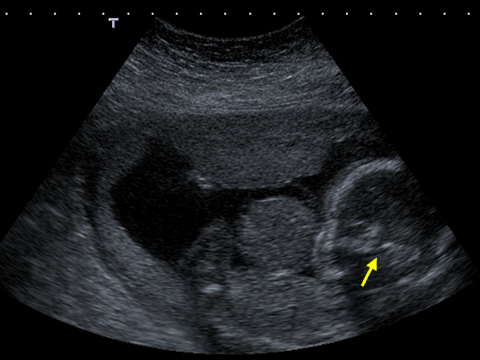

This axial scan through the fetal abdomen might lead you to believe that there are two babies lying side by side.